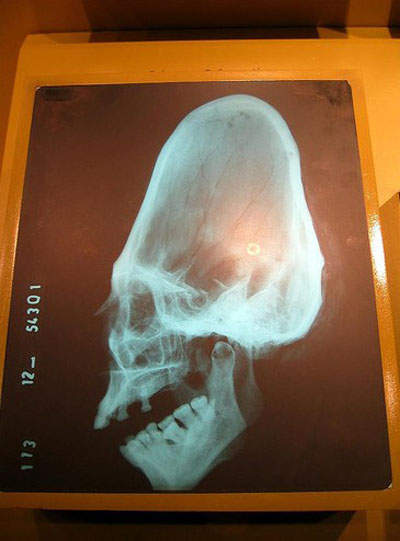

2.非洲的扁頭( cranial deformation)

聽說之前在這裡,一生下小孩,就會用石頭來打扁頭,所以當時這裡的地名就稱了扁頭